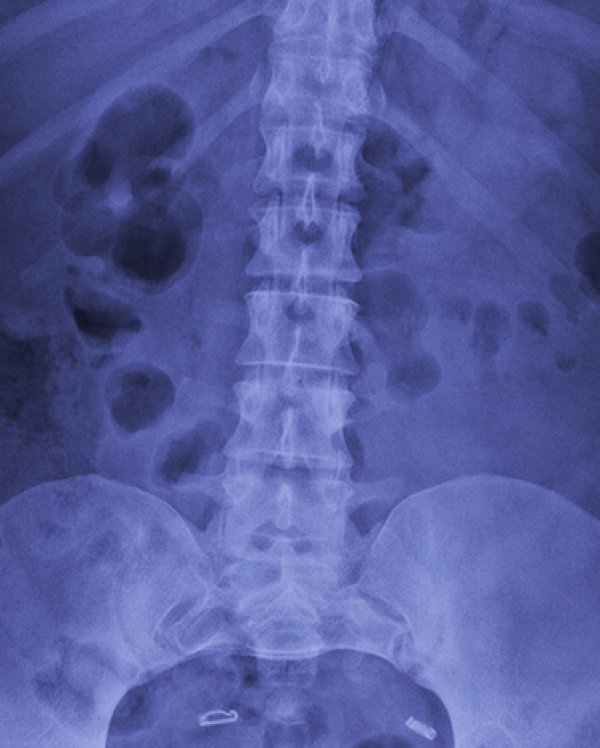

Čovek iz Brazila je prošle nedjelje posjetio bolnicu u Sao Paolu zbog bola u donjem dijelu kičme. Vjerovao je da je problem u diskus herniji i želio je da to snimi. Snimak je pokazao da je zaista u pitanju diskus hernija, ali i da čovjek ima tri bubrega sa kojima je rođen, a da to nije ni znao. Lijevi bubreg bio mu je sasvim u redu, a pokazalo se da ima i dva spojena desna bubrega.

Mokraćovodi, odnosno ureteri ovog muškarca, spojeni su na ulazu u bešiku.